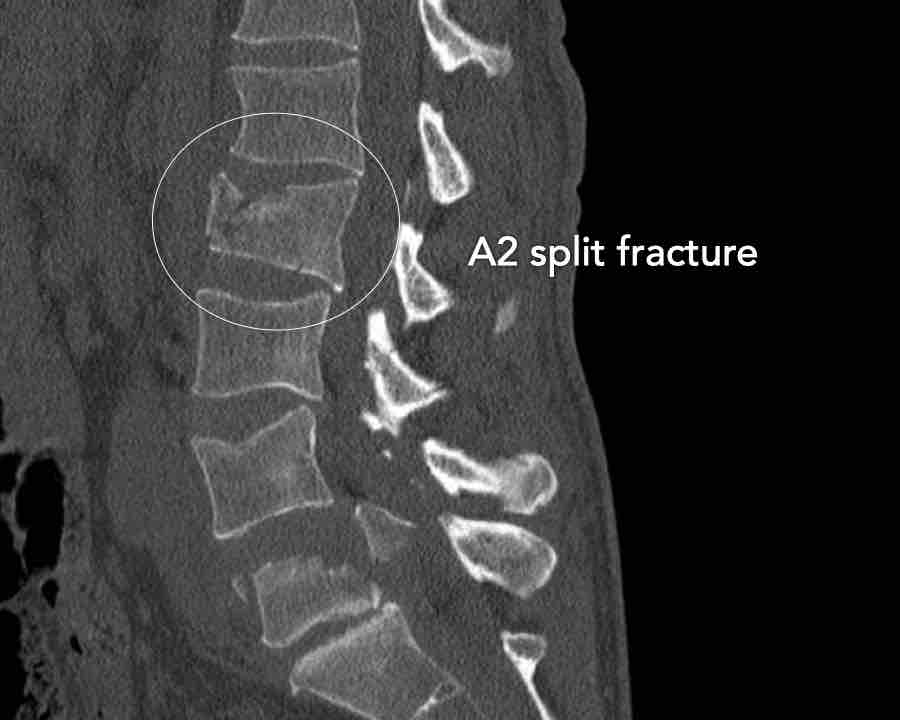

A2 Split fracture

A2 is a fracture of both endplates without involvement of the posterior wall of the vertebral body.

What is the highest AO-type of injury?

Findings:

- No C or B injury

- Fracture of the vertebral body with involvement of both endplates (1+1 points), no posterior wall involvement

Conclusion

injury type A2